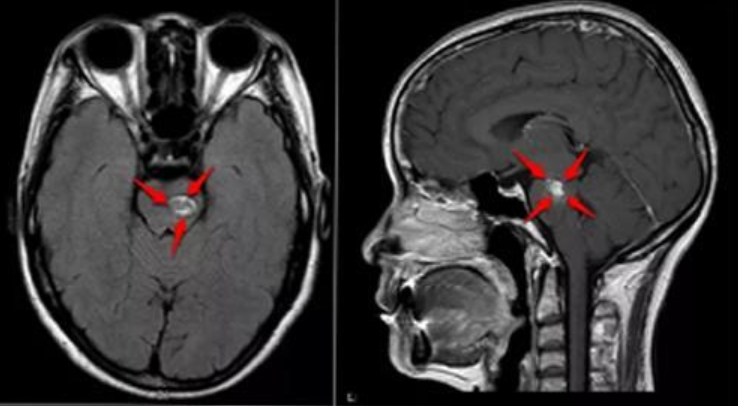

腦海綿狀血管瘤是指長(zhǎng)在腦內(nèi)的血管畸形,其中腦干部位的海綿狀血管瘤是位置較深、手術(shù)難度規(guī)模較大的顱內(nèi)海綿狀血管瘤,年出血率為4.6%,再出血間隔為3天-151個(gè)月。腦干海綿狀血管瘤約占顱內(nèi)海綿狀血管瘤的20%~30%,由于腦干位于顱腦中心血管神經(jīng)密集區(qū)域,被認(rèn)為是手術(shù)的禁區(qū),除了主刀醫(yī)生的選擇,一個(gè)好的手術(shù)時(shí)機(jī)也重要。那么,什么時(shí)候?yàn)槟X干海綿狀血管瘤出血手術(shù)治療的更佳時(shí)間呢?

腦干海綿狀血管瘤出血手術(shù)治療的更佳時(shí)間?在腦干海綿狀血管瘤具有多年經(jīng)驗(yàn),和上千例手術(shù)經(jīng)驗(yàn)的國際顱底腫瘤手術(shù)教授巴特朗菲教授表示,手術(shù)時(shí)機(jī)的把握是影響術(shù)后神經(jīng)功能恢復(fù)程度的重要因素,掌握適當(dāng)?shù)氖中g(shù)時(shí)機(jī)有助于提高手術(shù)療效,減少手術(shù)并發(fā)癥。腦干海綿狀血管瘤手術(shù)時(shí)機(jī)的選擇尚有爭(zhēng)議,多數(shù)學(xué)者認(rèn)為早期手術(shù)比延遲手術(shù)的效果要好。此時(shí)病灶周圍水腫已基本消退,血腫也明顯液化,病灶周邊含鐵血黃素膠質(zhì)增生帶已形成,而血腫尚未完全機(jī)化、周圍組織的玻璃樣變及纖維化,是實(shí)施手術(shù)的較好時(shí)期。另外國際專家認(rèn)為早期手術(shù)效果明顯優(yōu)于晚期,早期手術(shù)不僅切除病變相對(duì)容易,而且可較大限度地解除病灶( 腫瘤和出血) 造成的占位效應(yīng); 另外,隨著出血時(shí)間的延長(zhǎng),組織瘢痕化和血腫機(jī)化,使手術(shù)分離的界面變得模糊不清,增加手術(shù)難度; 因此,出血后10 ~ 30 天為更佳手術(shù)時(shí)間。也有報(bào)道將更佳手術(shù)時(shí)機(jī)選擇在腫瘤出血后 2 ~ 4 周之間進(jìn)行。國際專家比較了出血后早期( < 19 天) 手術(shù)與延遲手術(shù)的預(yù)后,認(rèn)為腦干海綿狀血管瘤早期手術(shù)效果較好。